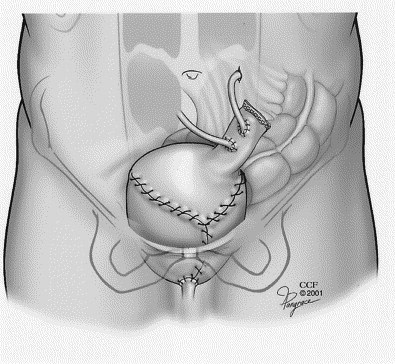

- En cambio si el tumor es infiltrante, e invade la pared muscular de la vejiga, se hace necesaria una cirugía más extensa para extirpar totalmente la vejiga: la cistectomía radical, a veces incluso con radioterapia o quimioterapia.